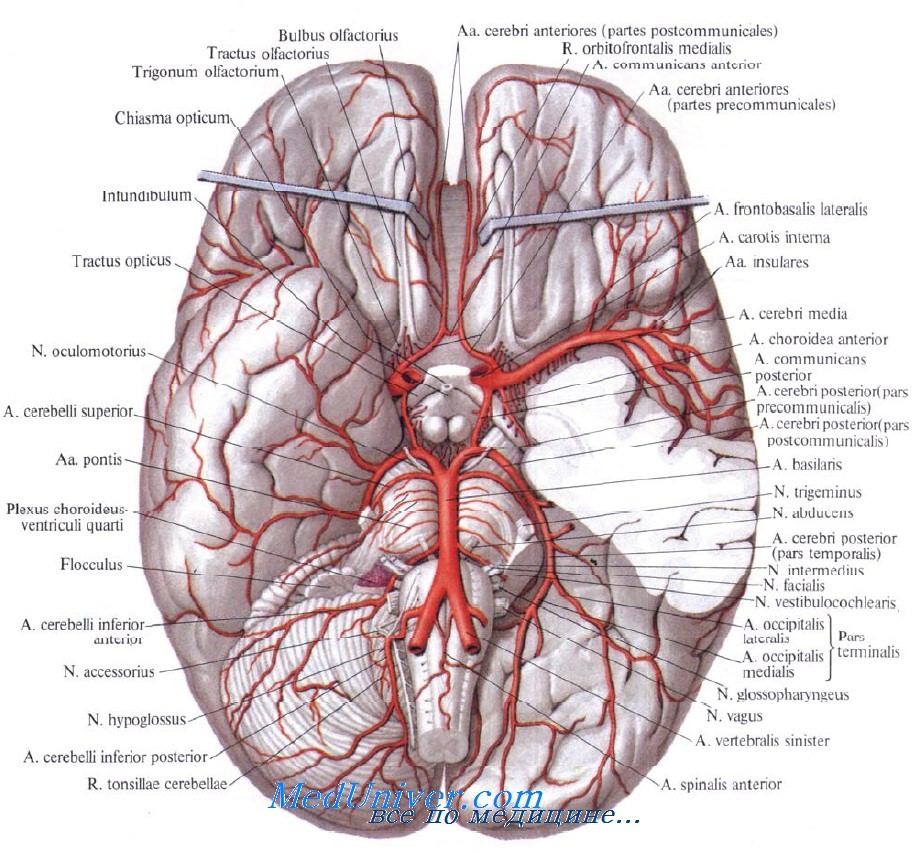

Анатомия: Задняя соединительная артерия мозга

:max_bytes(150000):strip_icc()/CircleofWillis-87378170-3ece0502a02949dd82310d723e0d4c98.jpg)

Раздел: Фотоэссе